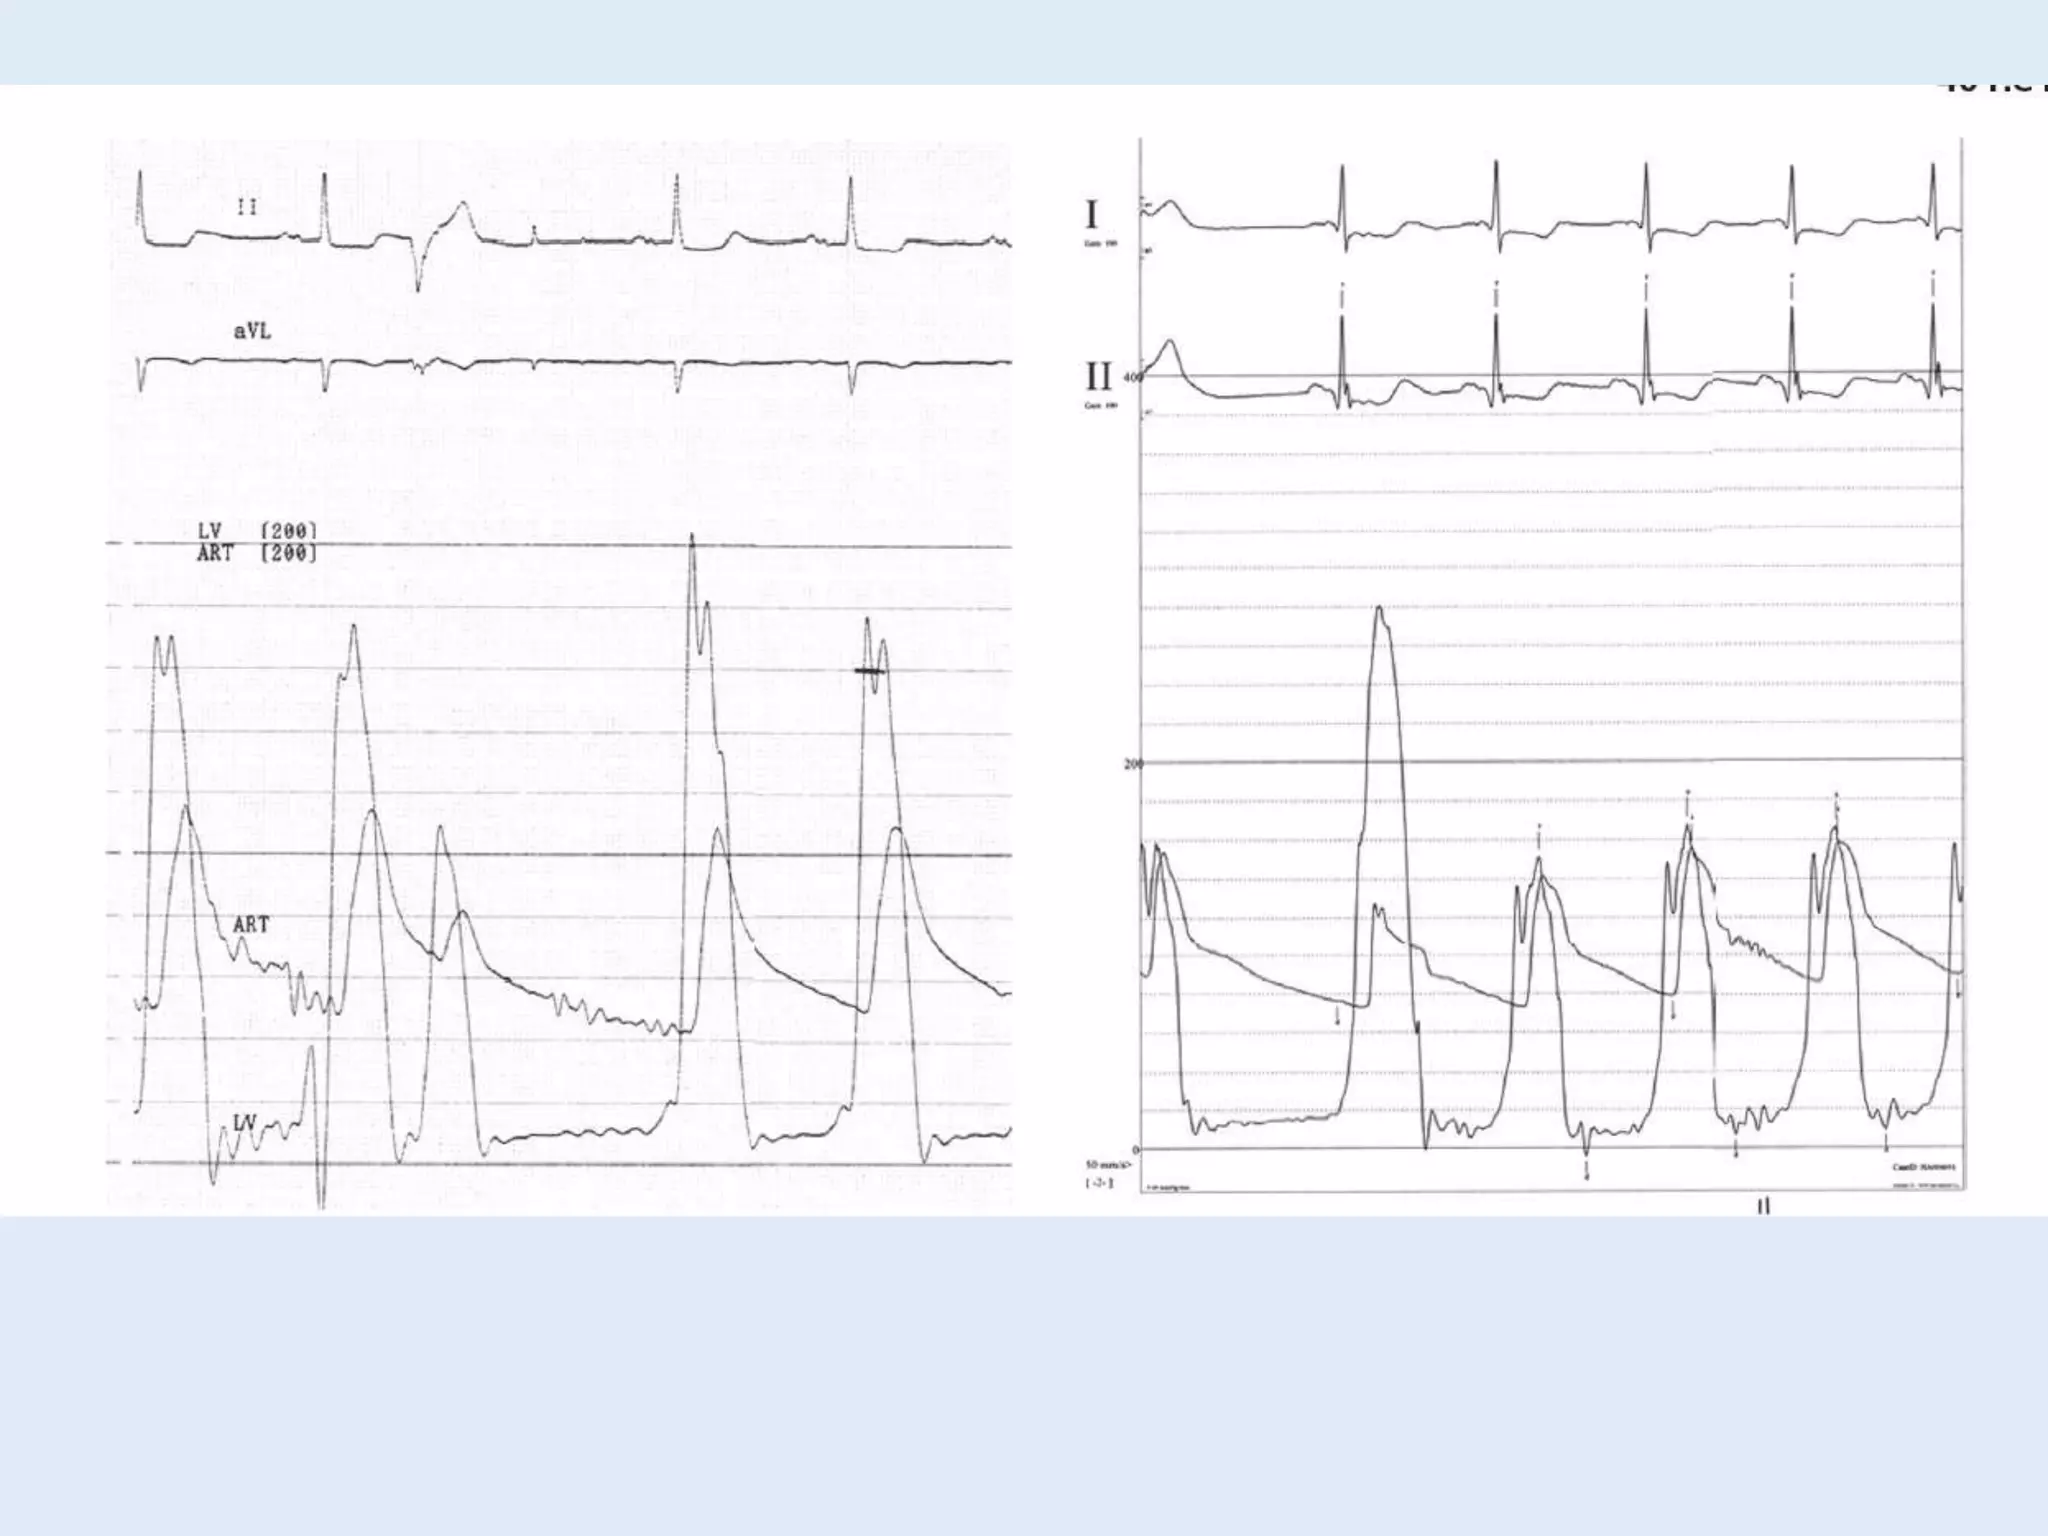

This document discusses right heart catheterization and the interpretation of pressure wave tracings from such a procedure. It notes that in a normal patient, right atrial and right ventricular pressure tracings will show smooth waves ranging and overshooting the right ventricular pressure. The tracing clearly shows the a wave of atrial contraction and the c wave of ventricular filling. It concludes by thanking the reader.